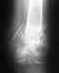

Спасибо огромное за скорый ответ. Все снимки были показаны сегодня 28.09.09 специалисту "УНИИ травматологии и ортопедии" (пока не знаю, кому именно, т.к. ездила не сама). Там порекомендовали операцию. Честно говоря, я была в ужасе и панике.

Не сочтите за недоверие, но с данными МРТ и снимками рентгена были ознакомлены ещё несколько ведущих врачей Екатеринбурских и Нижнетагильских больниц. И все они склоняются к мнению, что операция в моём случае не является необходимостью. Говорят, что травма начала срастаться правильно(уже прошёл месяц). У меня постельный режим, ношу корсет, делаю упражнения ЛФК по назначению.Спина почти не болит.

ПРи возможности выложу файлы со снимками.

Безусловно, перелом позвонка срастется без лечения. Проблемой является нарушение его формы, что приводит к изменению формы позвоночника. Отсутствие боли через месяц после травмы - это хорошо, но ни о чем судить не позволяет.